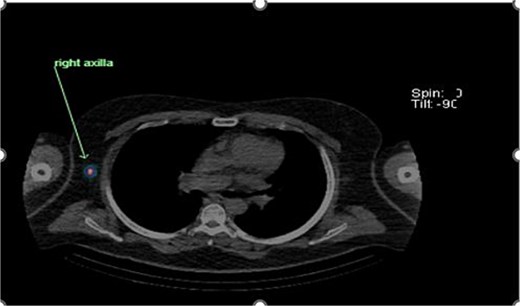

Preoperative lymphoscintigraphy was performed to detect the sentinel lymph node (Fig. 1), expecting it to be in the right inguinal region (Fig. 2). However, drainage to both the right axillary (Fig. 3) and inguinal areas was demonstrated. During surgery, a gamma camera confirmed drainage to both regions (Fig. 4). Blue dye was injected around the previous scar, and sentinel nodes were dissected guided by both blue dye and gamma camera for histopathology.

Unexpected drainage visualized toward the right axillary lymph nodes.

Intraoperative gamma probe confirming dual drainage to axillary and inguinal regions.

Histology showed no residual malignancy in the re-excision specimen. The right axillary node showed involvement by metastatic melanoma, while the groin lymph node was negative.